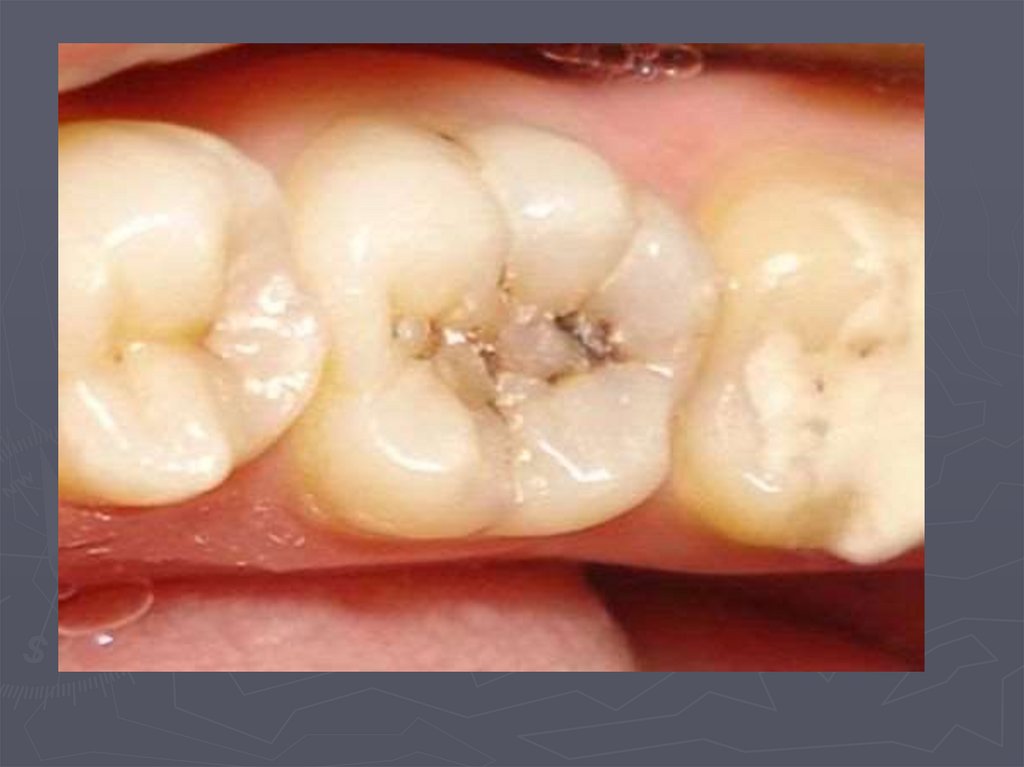

37. КЛИНИЧЕСКАЯ КАРТИНА СРЕДНЕГО КАРИЕСА при компенсированной форме:

► отмечается быстропроходящая боль от

химических, термических, иногда от

механических, раздражителей;

► края кариозной полости закругленные, ровные;

► эмаль плотная;

► дентин плотный, пигментированный;

► при зондировании болезненность определяется

по эмалево-дентинному соединению.